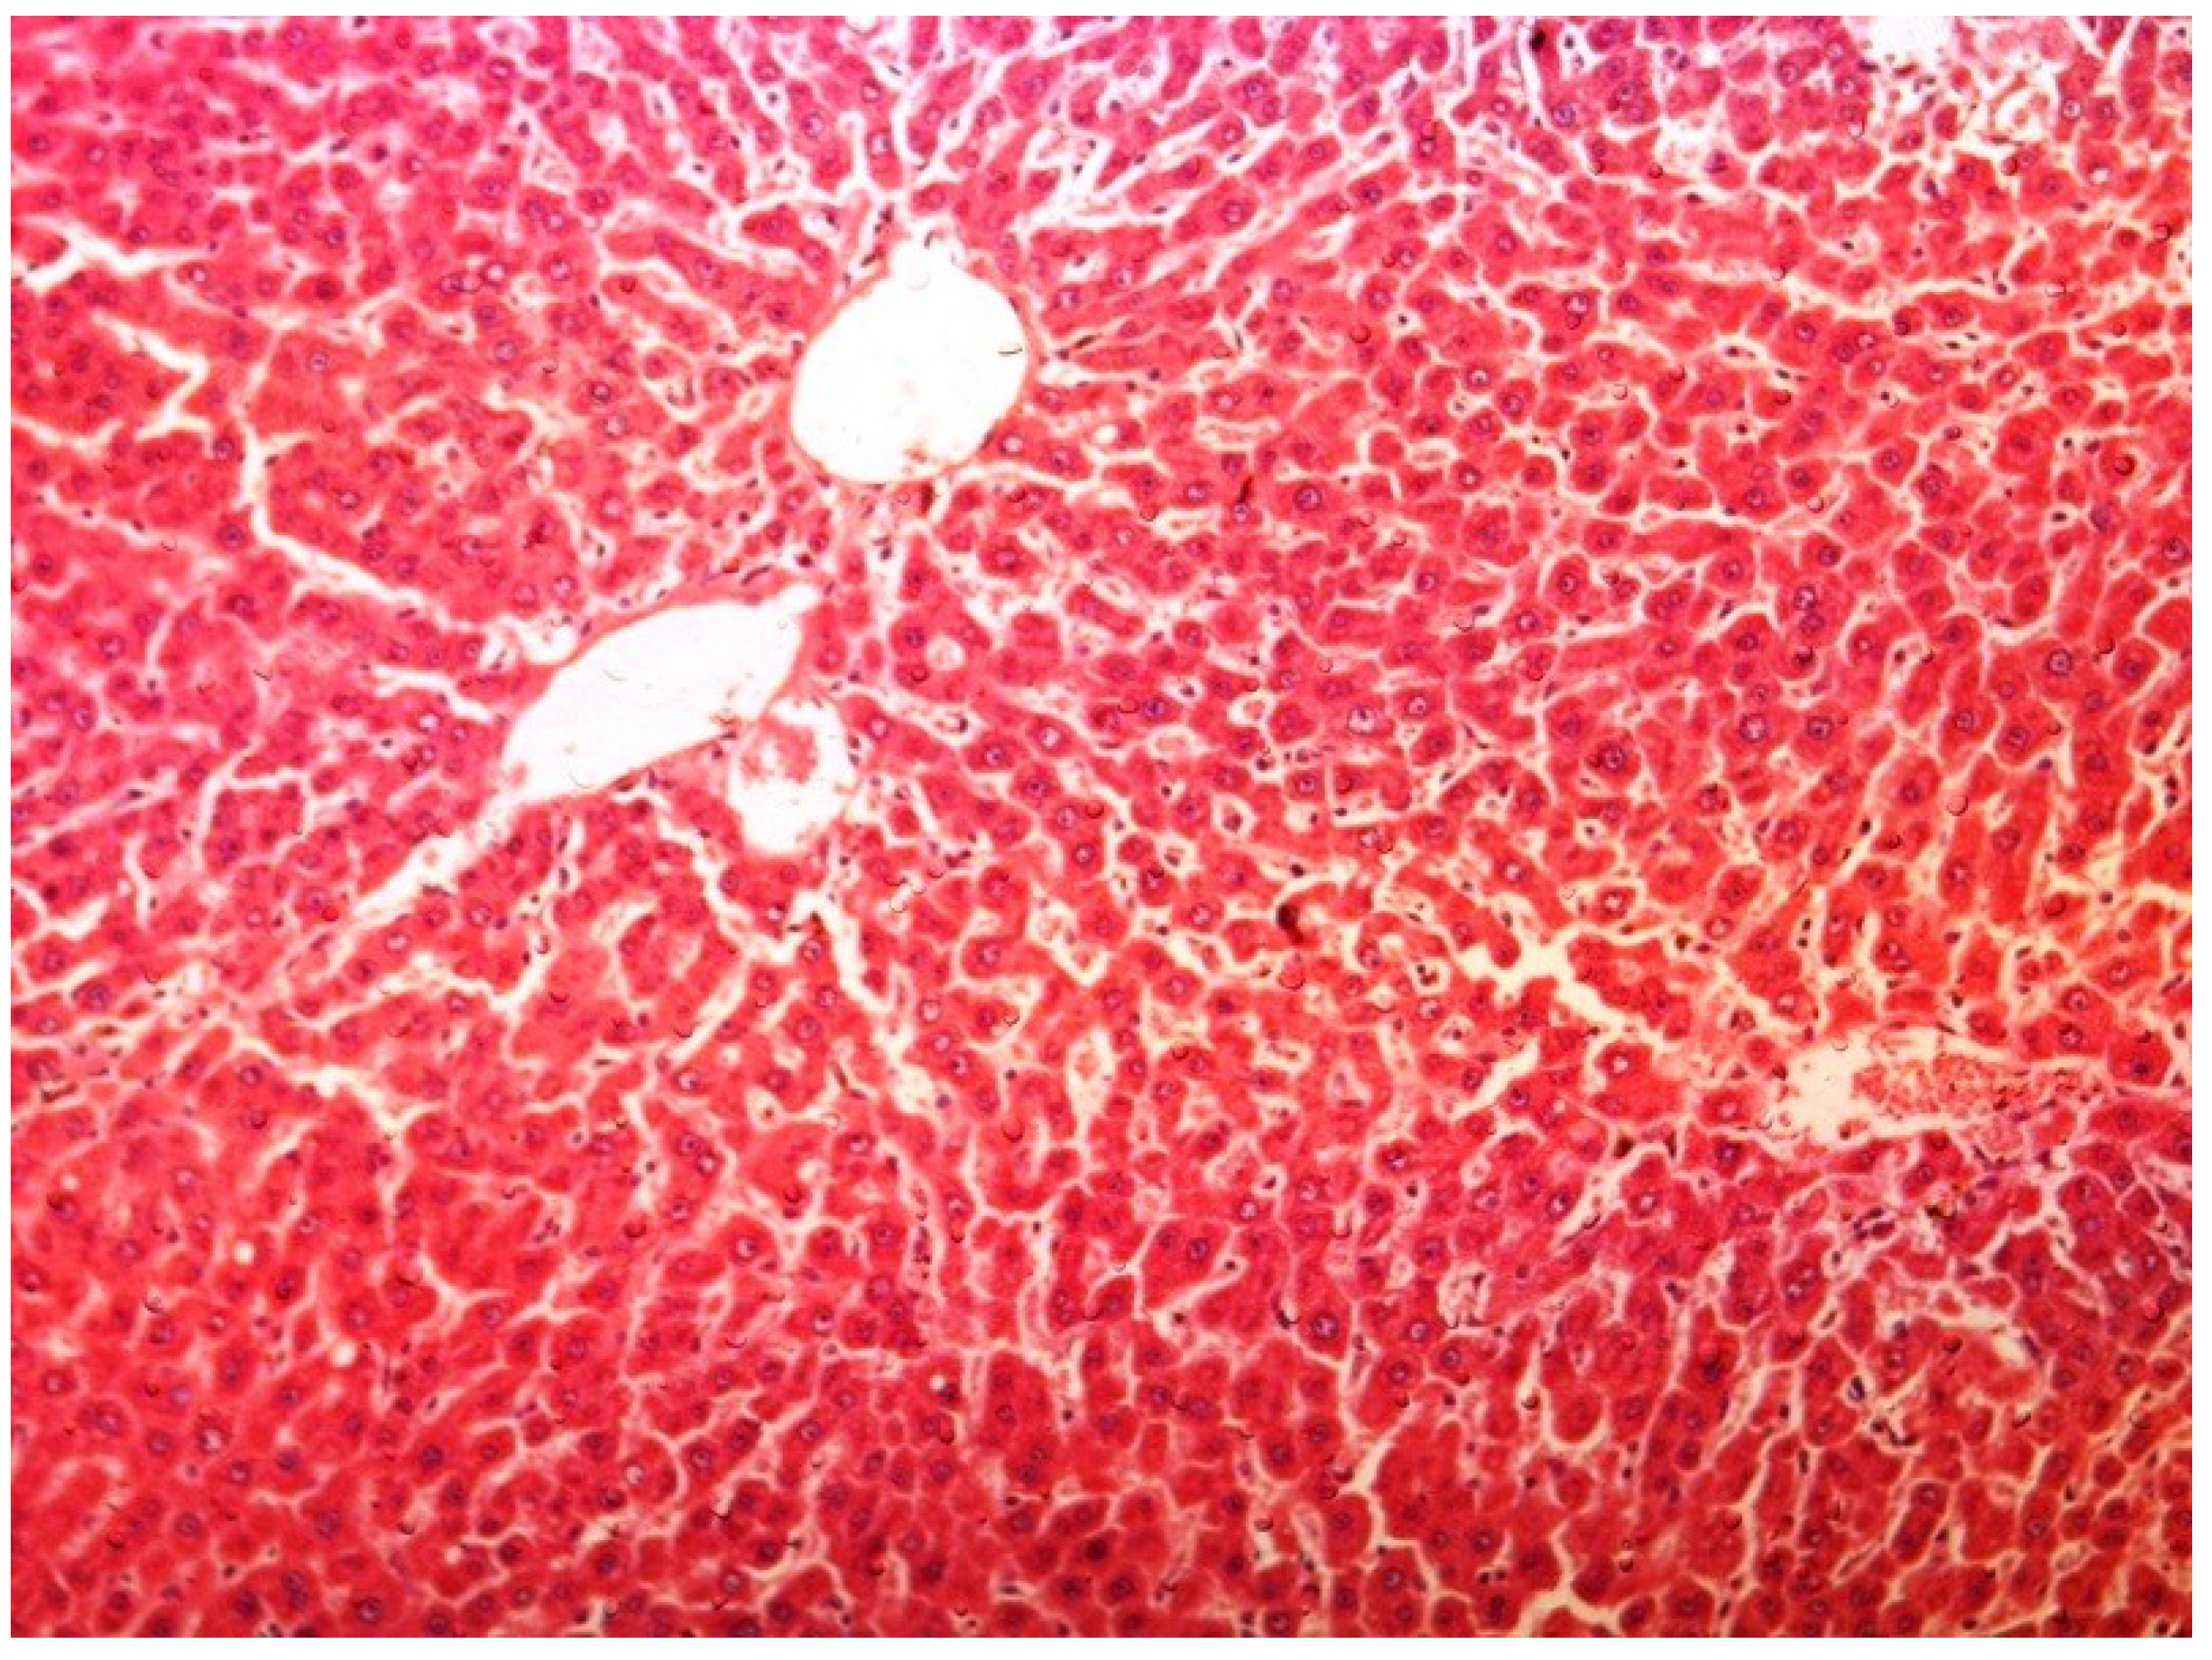

The histopathology of CCl4-induced rats when compared to normal hepatic architecture (Figure 2) showed massive fatty changes, necrosis, ballooning degeneration and the loss of cellular boundaries (Figure 3). The liver sections of plumieride at the dose level of 5 mg/kg body weight plus CCl4-treated rats (Group III) showed mild prevention of CCl4-induced degenerative changes with the few pyknotic nuclei and fatty vacuolizations in the cytoplasm (Figure 4). The liver sections of plumieride treated rats at the dose level of 10 mg/kg body weight along with CCl4 (Group IV) indicated partial amelioration of degenerative effects in hepatocytes but still show cloudy swelling and mild fatty changes (Figure 5). The histomorphological picture of liver sections of plumieride at the dose level of 20 mg/kg body weight along with CCl4-induction to rats (Group V) showed more or less normal labular patterns devoid of degenerative changes, and cytoplasm was preserved with prominent nucleus without intracellular lipid accumulation (Figure 6) almost comparable to the normal control and silymarin treated Group VI (Figure 7).

Figure 3.

Photomicrograph of rat liver section with CCl4 treatment showing ballooning degeneration and distended portal vein, mild periportal fibrosis and necrosis at H & E × 100.